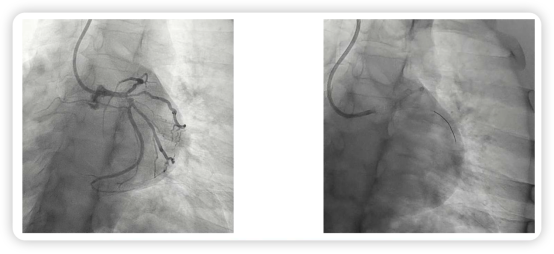

鉴于患者在运动过程中即诱发了典型症状,治疗团队评估继续运动负荷试验风险过高,因此直接进入有创评估流程——冠状动脉造影。结果显示:左主干远端存在三分叉病变(图2),属于高危解剖类型。

图2.患者冠状动脉造影结果